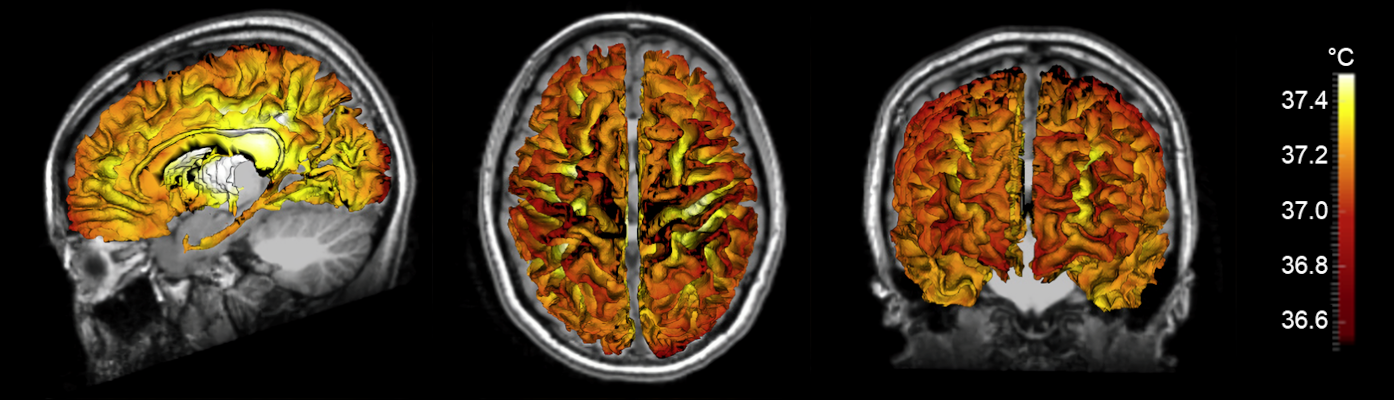

Figure 1. Simulated human brain temperature maps. Individual brain tissue and vessel structure acquired with MRI in a healthy human volunteer was used as input data for our fully conserved biophysical model. From left to right: sagittal, axial, and coronal views.

Our model accounts for heat transfer within the brain via conduction, convection, and advection, and was calculated in three physical domains: arteries, tissue, and veins. Individual vessel and tissue structure was obtained from MRI data collected from each subject, and vasculature was augmented using a randomly exploring rapid tree algorithm. Vessel structure maps were used to generate flow rates throughout the blood vessel network, as cerebral blood flow is the primary mechanism for heat dissipation in the brain. Heat generation is the result of cerebral metabolism, and tissue structure maps were used in a similar manner to calculate local metabolic rates. Finally, steady-state equations for each domain were formulated to ensure local and global energy conservation and solved to calculate 3D temperature distributions. The primary finding of this study was the observation that temperature magnitude and spatial patterns differ between individuals, further supporting the need for a personalized approach to brain temperature management. Our modeling efforts were accompanied by experimental MR brain thermometry in healthy humans, and temperature measurements were similar to model predictions.